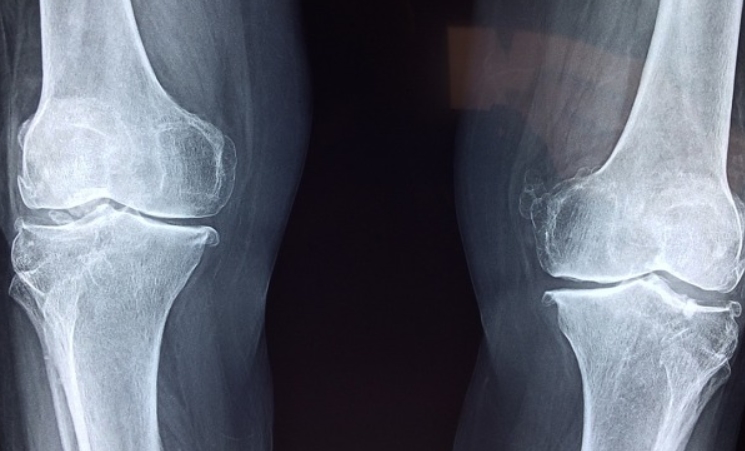

상어 연골, 소 연골, 철갑상어 중 어떤 원료가 나에게 맞을지 고민되셨다면, 아래 내용을 참고해보시면 도움이 될 거예요. 상어 연골은 항염 작용이 뛰어나고 콜라겐과 칼슘 등 다양한 보조 성분이 함께 들어 있어 복합적인 관절 보호 효과를 기대할 수 있어요. 하지만 알레르기 반응이 나타날 수 있고, 윤리적 소비를 중시하는 분들에게는 고민이 될 수 있습니다.

반면 소 연골은 가장 대중적인 원료로, 흡수율도 높고 가격도 합리적이라 입문용으로 많이 선택돼요. 실제로 많은 관절 영양제가 소 연골을 기반으로 만들어지고 있어요. 철갑상어는 상대적으로 희귀한 고급 원료로, 고순도 제품에서 주로 사용됩니다. 흡수율이 뛰어나고 체감 효과가 빠르다는 후기가 많지만 가격이 높은 편이라 부담이 될 수 있어요. 각 원료마다 장단점이 뚜렷하기 때문에, 예산과 개인 체질, 복용 목적에 따라 선택하면 좋습니다.